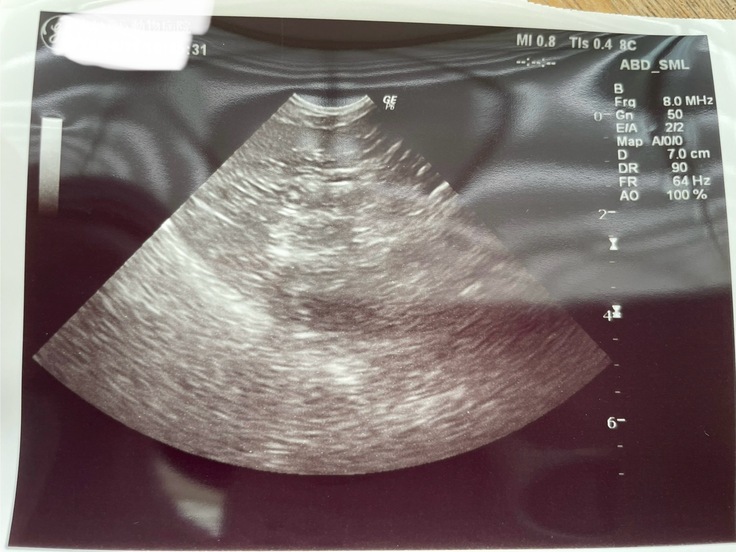

金曜日かかりつけ医に相談して再発の可能性もあるので指定項目と腹部エコーする様にご指示いただき地元の病院で検査をしてきました。

血液検査、腹部エコー、触診、口内検査、耳検査をしましたがアッシュ特に問題はありませんでした。ステラも問題なかったです。

下記、今回の領収書となります。